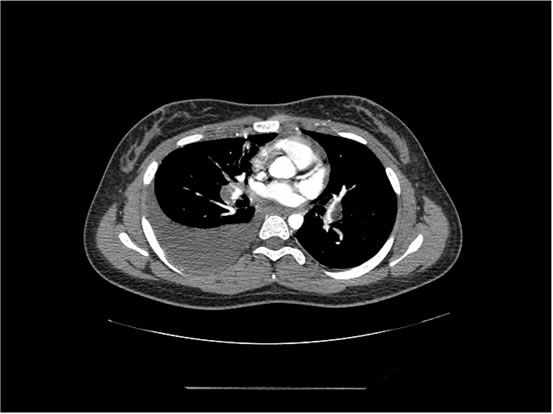

We ordered a CT scan with infusion of the chest

I will show you 12 CT-scan cuts.